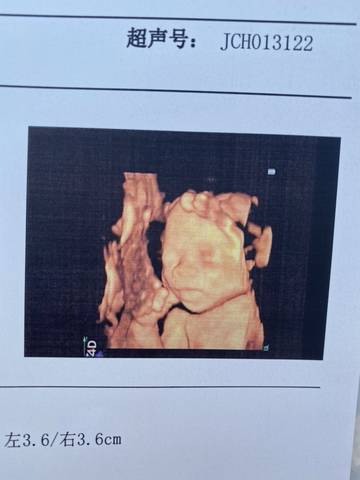

大家快来看看我儿子的四维照,可不可爱

journal_insert_pic_1676859234journal_insert_pic_1676859344